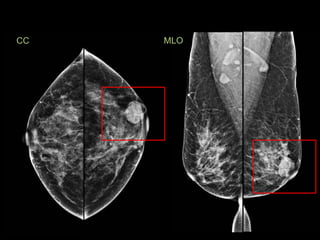

Proyección craneo-caudal (CC)

Proyección mediolateral-olblicua (MLO)

Proyección craneo-caudal (CC) Proyecciónmediolateral-olblicua (MLO)